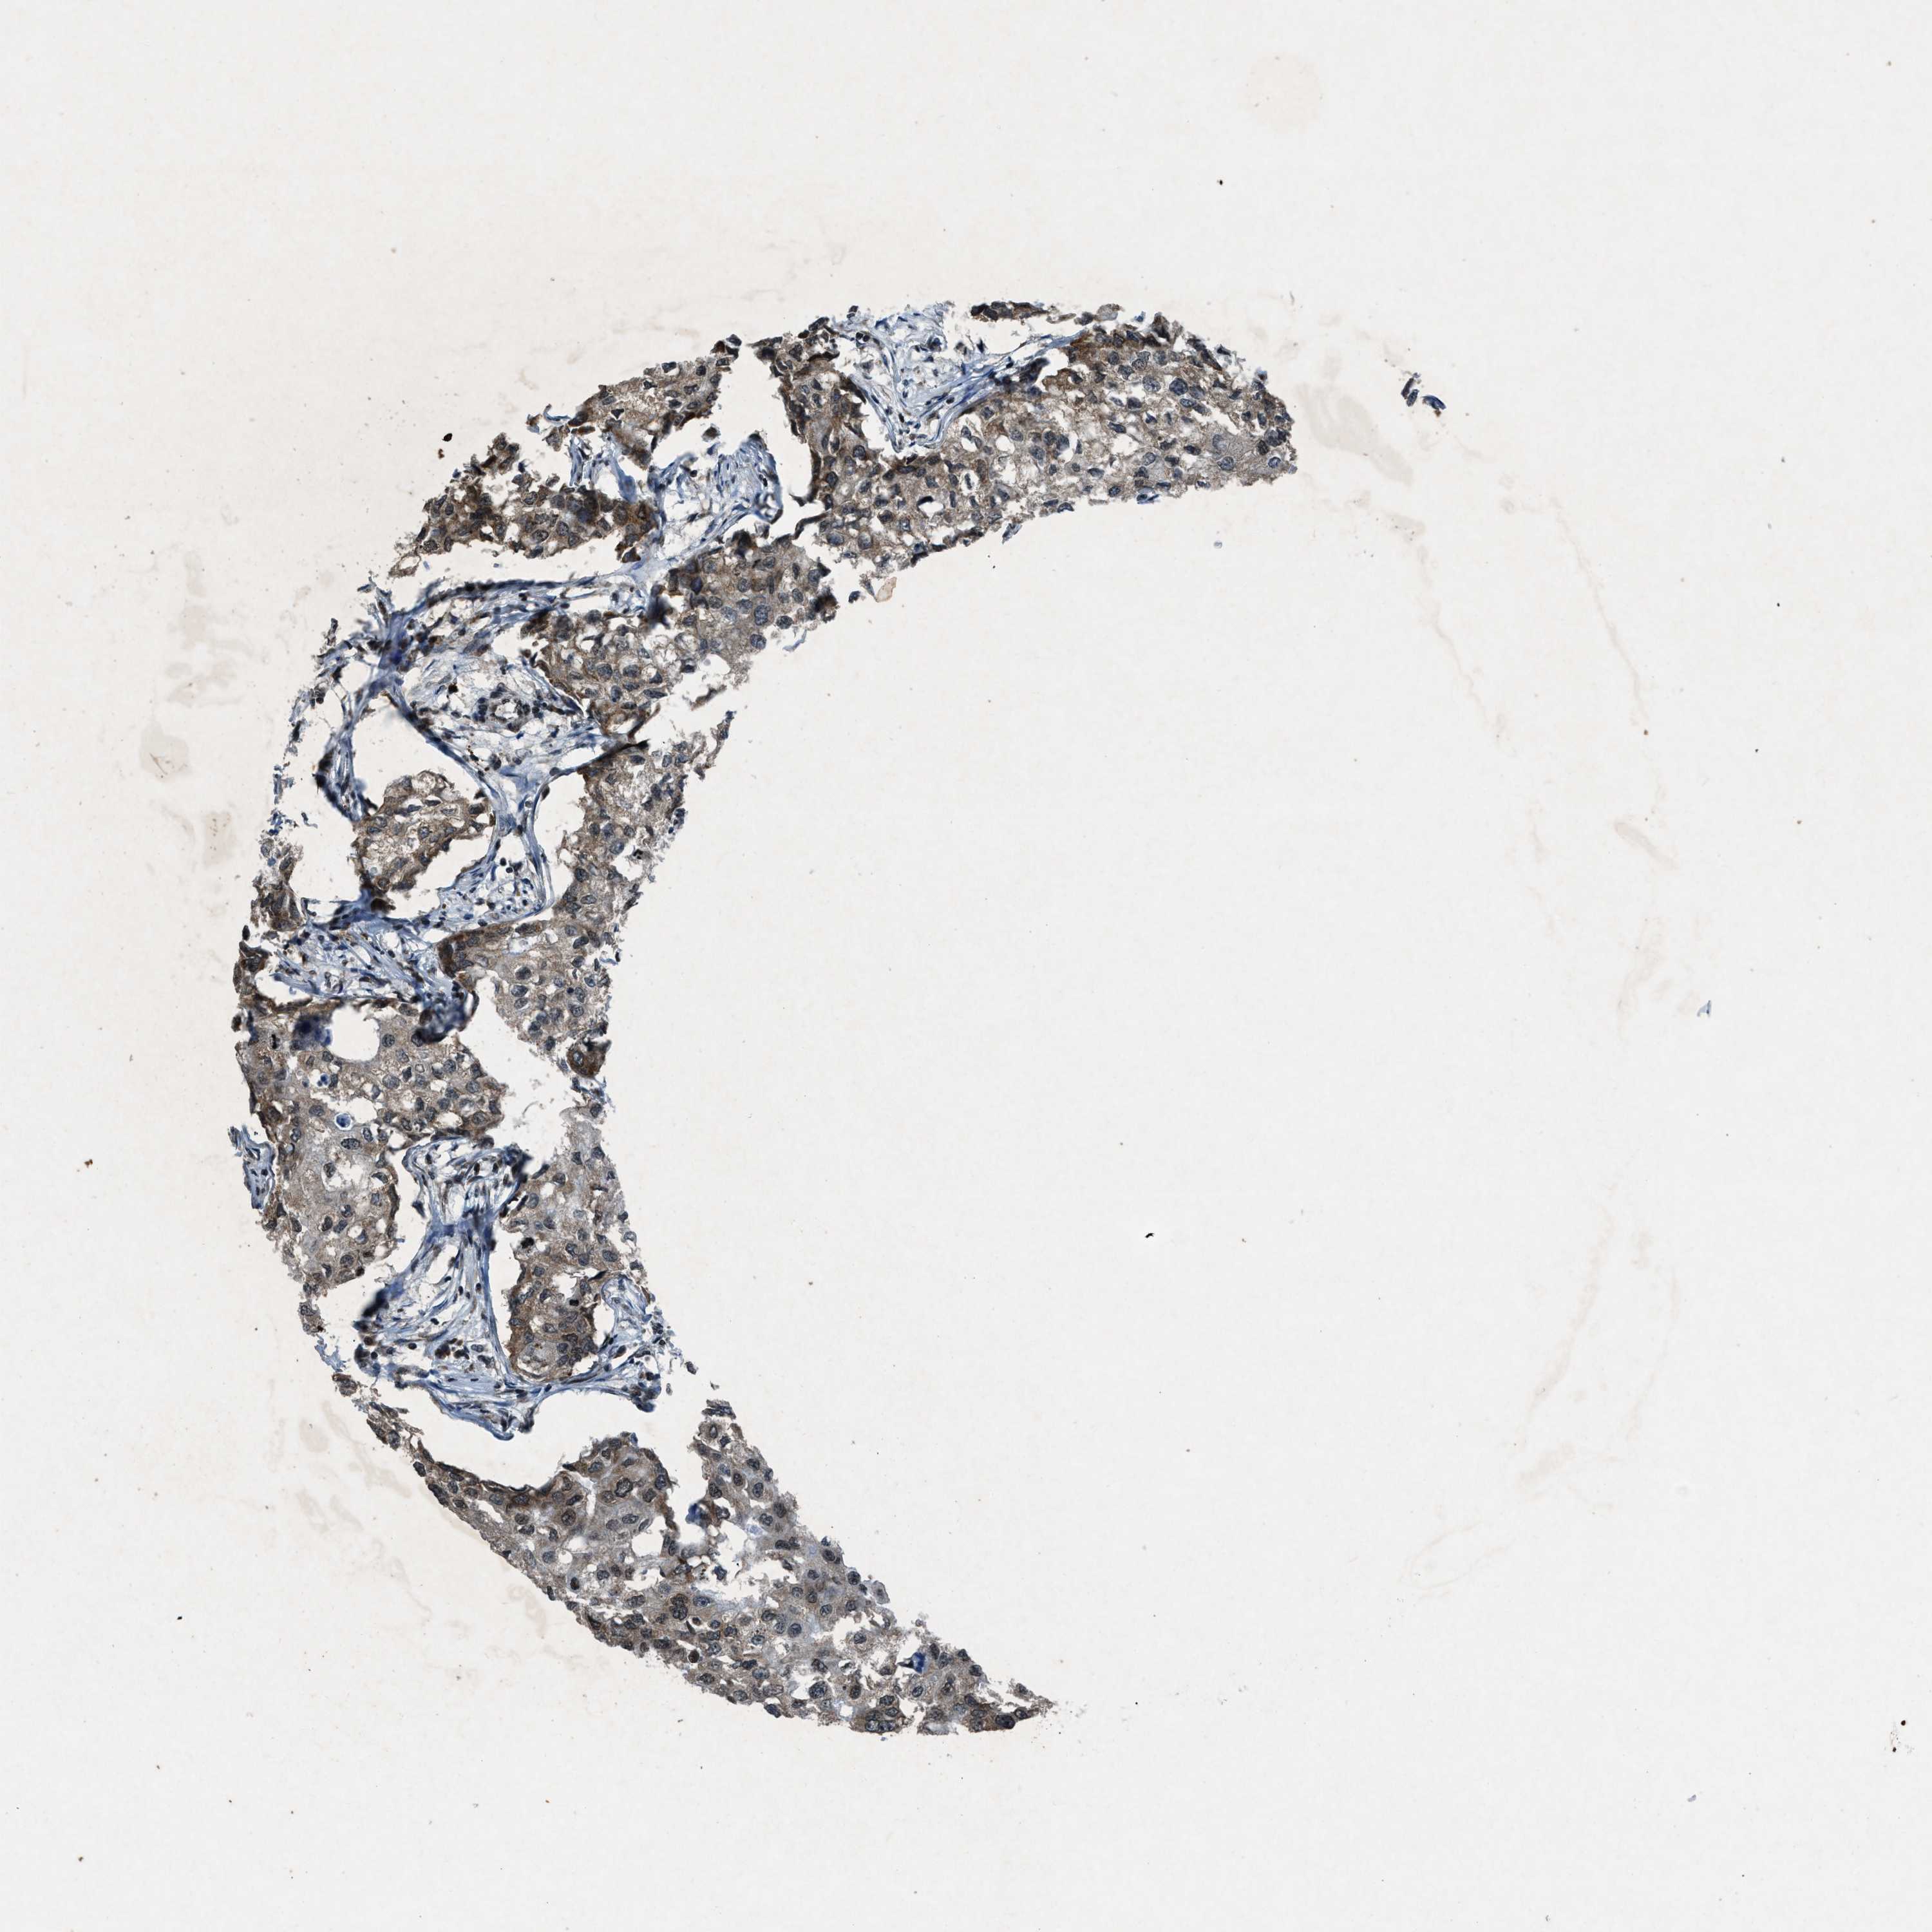

BRCA TCGA BRCA VALIDATION PROTEIN EXPRESSION